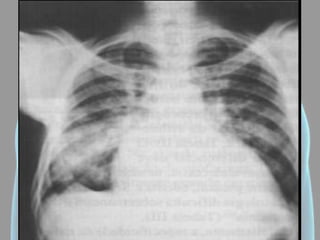

Atelectasia

• Hipertransparência (um

hemitórax; toda área

pulmonar; pequenas

áreas);

• Colapso Alveolar;

• Diminuição dos espaços

intercostais;

• Desvio do mediastino

ipsilateral;

• Elevação da hemicúpula

diafragmática (se for em

base).

Atelectasia • Hipertransparência (um hemitórax;toda área pulmonar; pequenas áreas); • Colapso Alveolar; • Diminuição dos espaços intercostais; • Desvio do mediastino ipsilateral; • Elevação da hemicúpula diafragmática (se for em base).